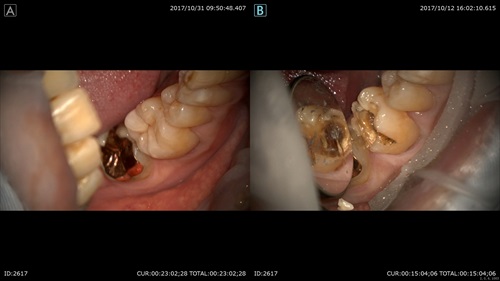

マイクロスコープだと目の前でこの様に術前(右)術後(左)をお見せできるので分かりやすいですね。

今日もすべての患者さまにご満足頂くためにマイクロスコープは欠かせません。

このように当院では「今日どのような治療をしたのか」を必ず、毎回プレゼンテーションしています。